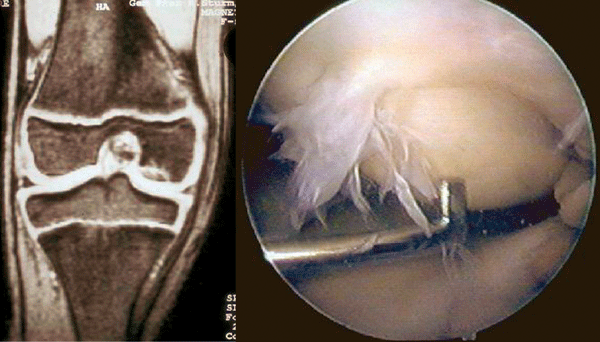

Als wichtige Differenzialdiagnose der Arthrose bei jüngeren Patienten nennt der Experte die Osteochondrosis dissecans. Sie manifestiert sich meist gegen Ende des Wachstums, selten im Kindesalter oder jenseits des 50. Lebensjahres. Eine aseptische Nekrose im subchondralen Knochen führt dazu, dass der bedeckende Knorpel als freier Gelenkkörper („Gelenkmaus“) abgestoßen wird. Betroffene klagen v.a. über Belas­tungsschmerzen und Blockierungen.

Freie Gelenkkörper lassen sich nur selten tasten, sind aber im MRT lokalisierbar. Patienten mit stabilem Dissektat werden bis zum Abschluss des Wachstums konservativ behandelt. Eine absolute OP-Indikation stellt die Ablösung oder Instabilität des Dissektats dar, auch eine knorpelchirurgische Therapie ist möglich.

Bei der Osteochondrosis dissecans ermöglicht die MRT (links) die exakte Lokalisation, Verlaufskontrolle und Einschätzung der Vitalität. Eine genauere Beurteilung gelingt mittels Arthroskopie (rechts). Bei der Osteochondrosis dissecans ermöglicht die MRT (links) die exakte Lokalisation, Verlaufskontrolle und Einschätzung der Vitalität. Eine genauere Beurteilung gelingt mittels Arthroskopie (rechts). © Jerosch J. internistische praxis 2018; 59: 253-272; © Mediengruppe Oberfranken – Fachverlage GmbH & Co. KG, Kulmbach